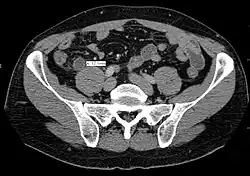

A CT scan demonstrating acute appendicitis (note the appendix has a diameter of 17.1 mm and there is surrounding fat stranding).

Where it is readily available, computed tomography (CT) has become frequently used, especially in people whose diagnosis is not obvious on history and physical examination. Although some concerns about interpretation are identified, a 2019 Cochrane review found that the sensitivity and specificity of CT for the diagnosis of acute appendicitis in adults was high.[63] Concerns about radiation tend to limit use of CT in pregnant women and in children, especially with the increasingly widespread usage of MRI.[64][65]

The accurate diagnosis of appendicitis is multi-tiered, with the size of the appendix having the strongest positive predictive value, while indirect features can either increase or decrease sensitivity and specificity. A size of over 6 mm is both 95% sensitive and specific for appendicitis.[66]

However, because the appendix can be filled with fecal material, causing intraluminal distention, this criterion has shown limited utility in more recent meta-analyses.[67] This is as opposed to ultrasound, in which the wall of the appendix can be more easily distinguished from intraluminal feces. In such scenarios, ancillary features such as increased wall enhancement as compared to adjacent bowel and inflammation of the surrounding fat, or fat stranding, can be supportive of the diagnosis. However, their absence does not preclude it. In severe cases with perforation, an adjacent phlegmon or abscess can be seen. Dense fluid layering in the pelvis can also result, related to either pus or enteric spillage. When patients are thin or younger, the relative absence of fat can make the appendix and surrounding fat stranding difficult to see.[67]